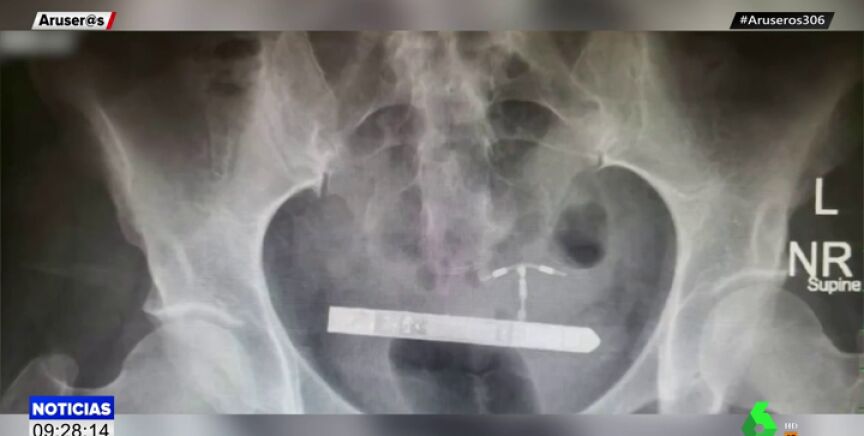

La afectada se introdujo el vibrador de nueve centímetros accidentalmente y llegó hasta la vejiga por la uretra. El ginecólogo que intervino en la operación ha asegurado que "nunca había visto un caso como este en toda su carrera".

El experto ha contado que primero buscaron el objeto en la vagina, pero que gracias a una radiografía descubrieron que se encontraba en la vejiga de la paciente.